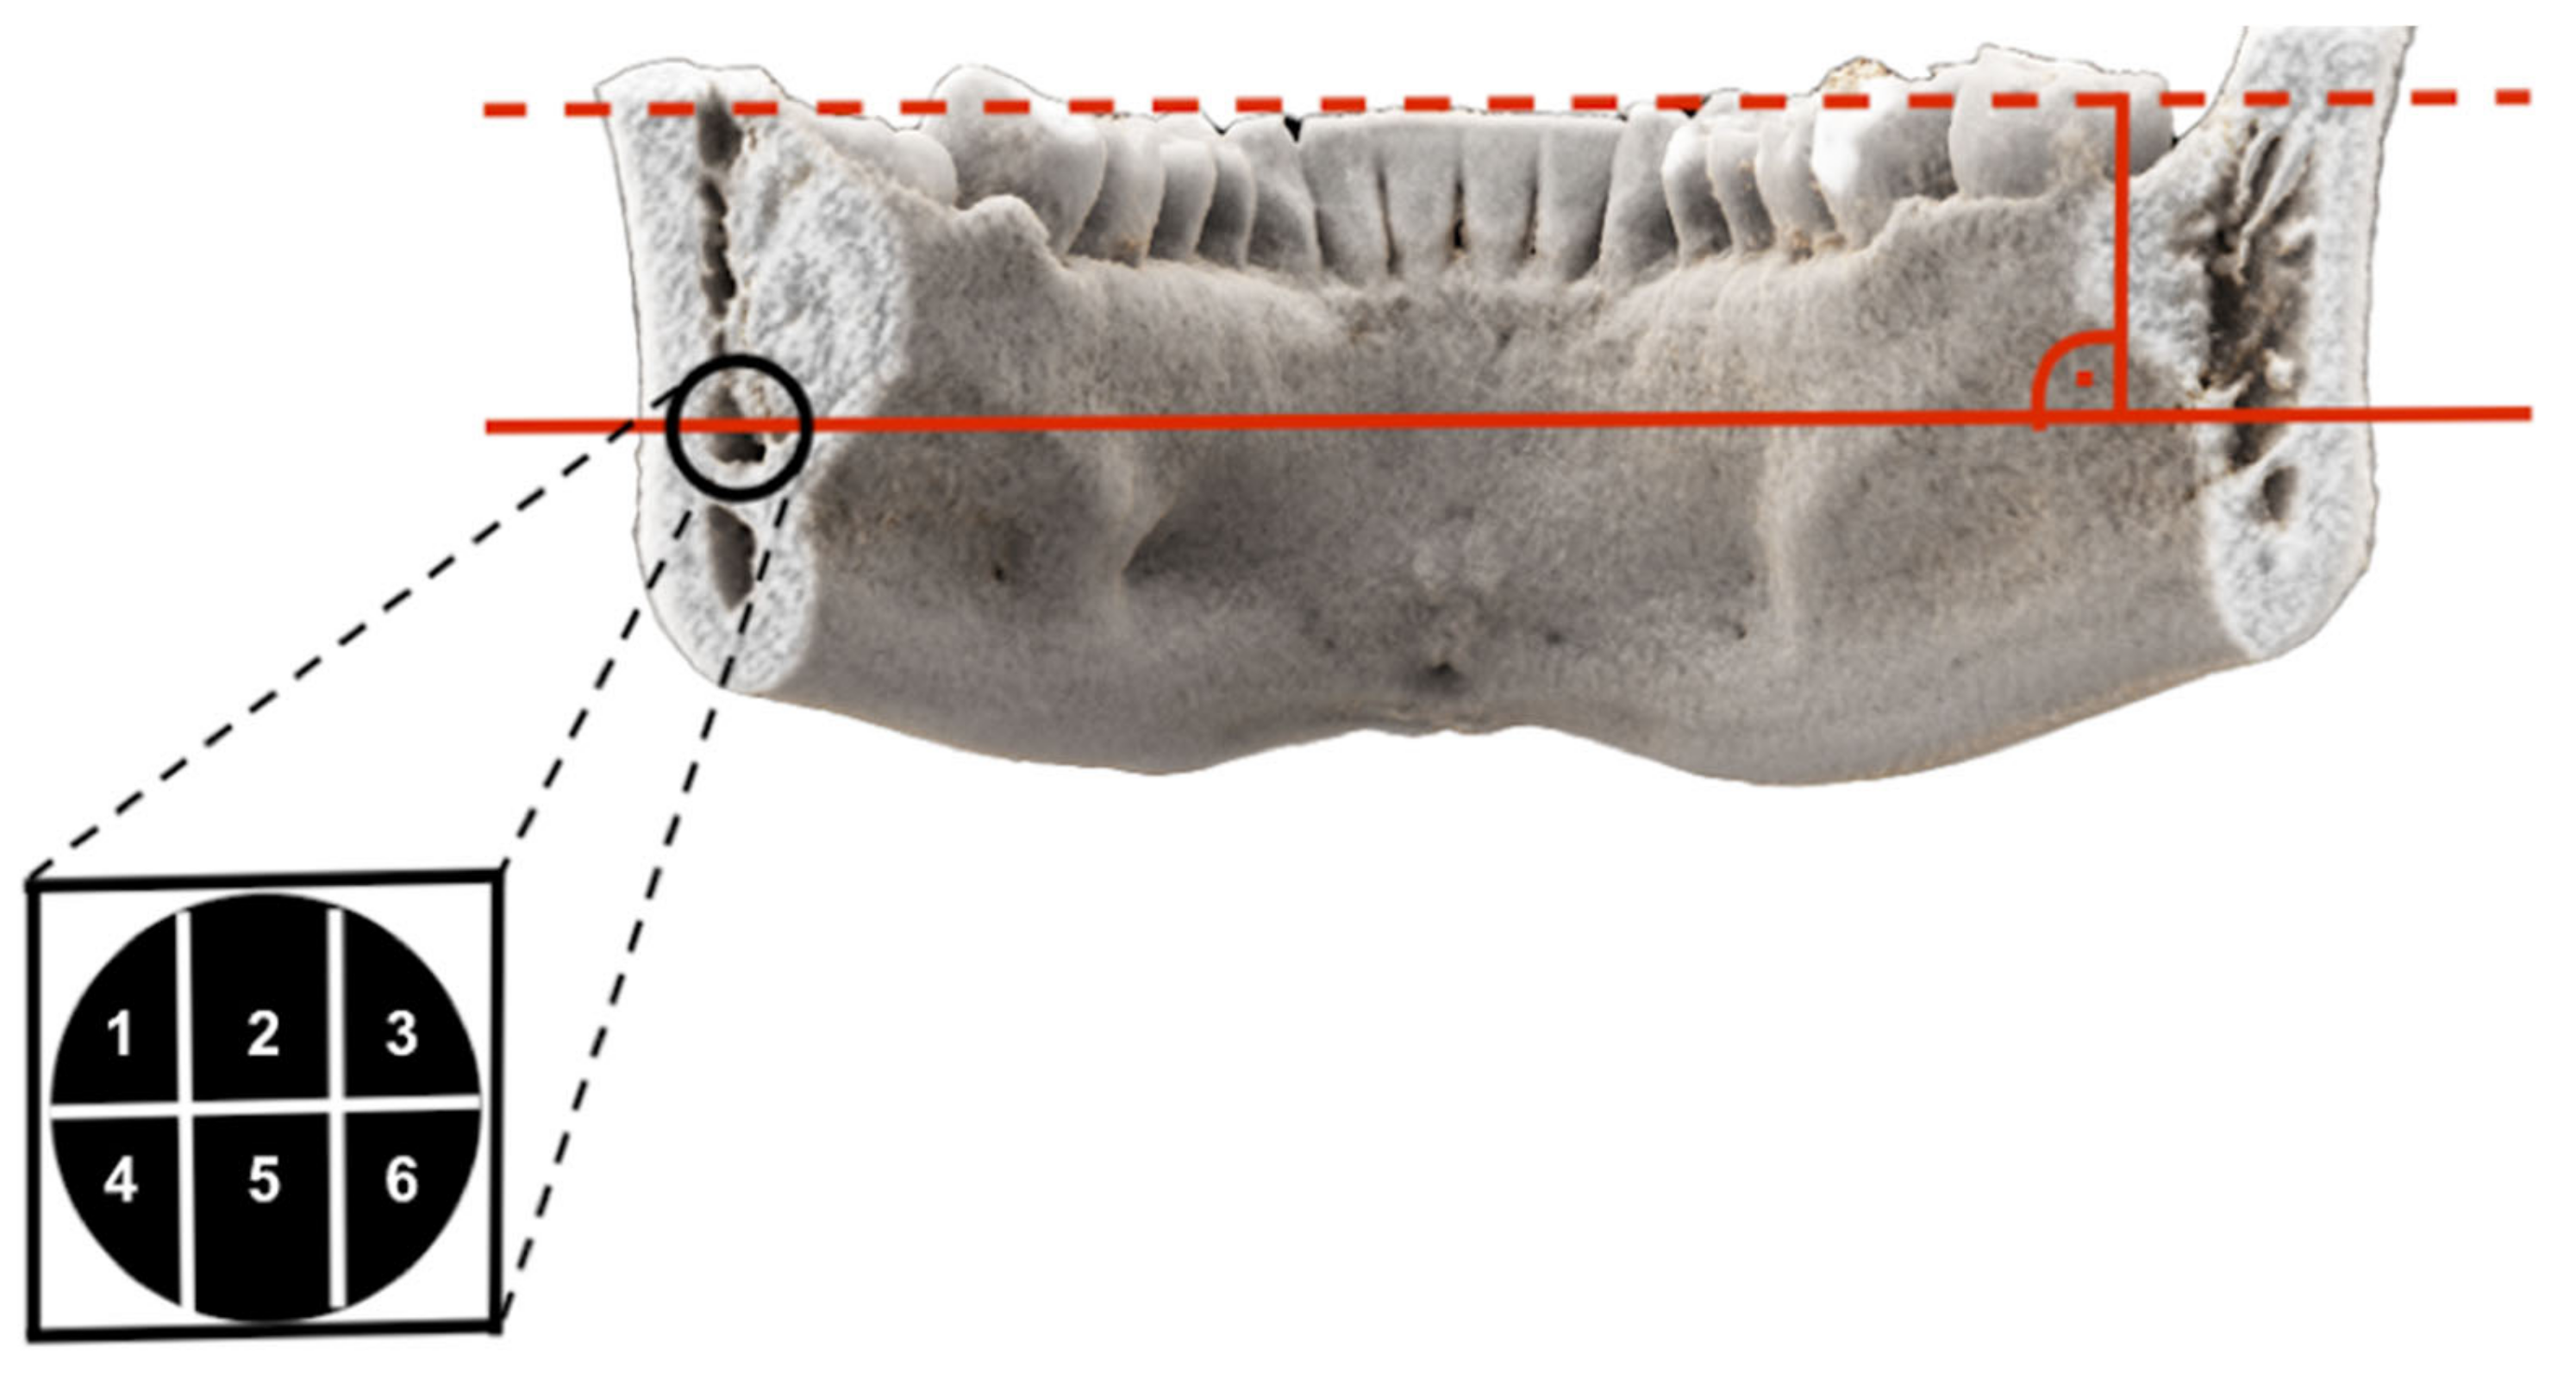

| Third Molar | Segment 1 | Segment 2 | Segment 3 | Segment 4 | Segment 5 | Segment 6 |

|---|---|---|---|---|---|---|

| Generally Yes | 78.9% | 97.4% | 47.4% | 68.4% | 100% | 65.8% |

| If Segment 1 Yes | - | 93.3% | 53.3% | 70% | 96% | 63.3% |

| If Segment 2 Yes | 78.4% | - | 48.7% | 67.6% | 100% | 67.6% |

| If Segment 3 Yes | 88.9% | 100% | - | 61.1% | 100% | 100% |

| If Segment 4 Yes | 88.5% | 96.2% | 46.2% | - | 100% | 69.2% |

| If Segment 5 Yes | 78.9% | 97.4% | 52.6% | 65.8% | - | 65.8% |

| If Segment 6 Yes | 84% | 100% | 72% | 72% | 100% | - |